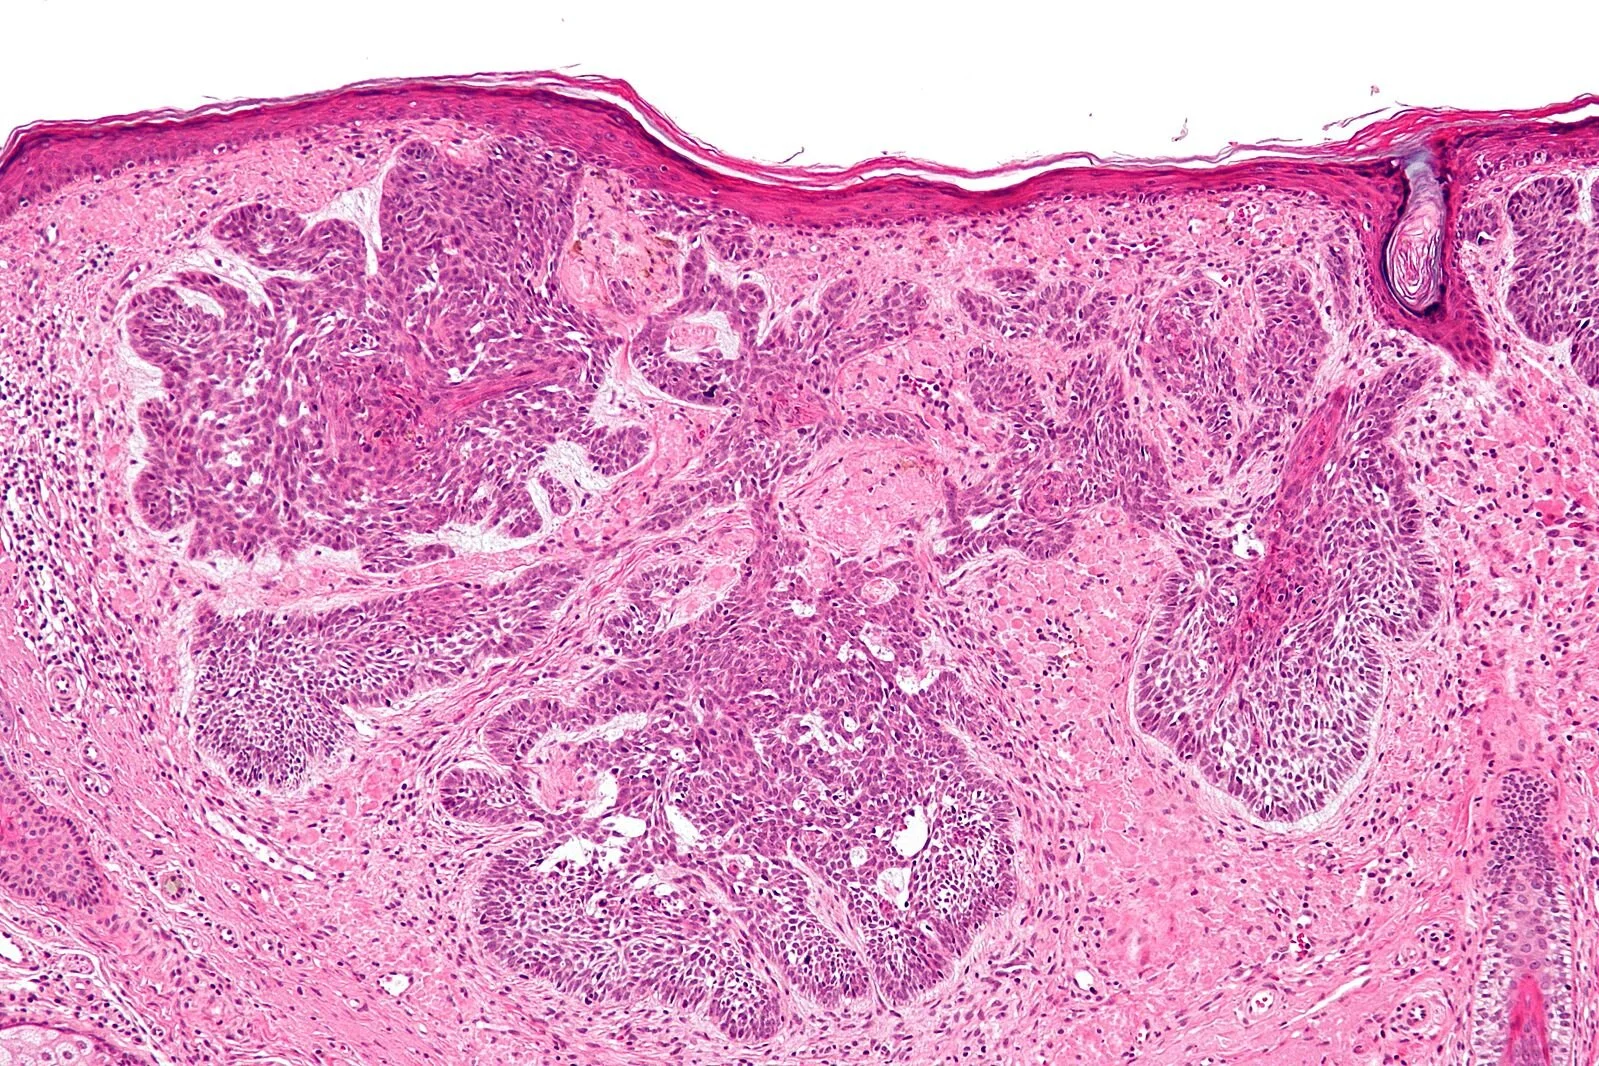

Main Type of Skin Cancer — Their Differences, Histology and Prevention